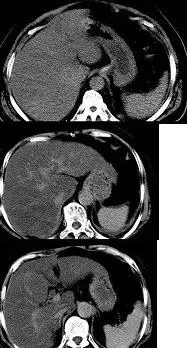

肝硬化影像学表现

多图读懂肝硬化的影像学表现

早期肝硬化伴肝内胆管结石

肝硬化腹水